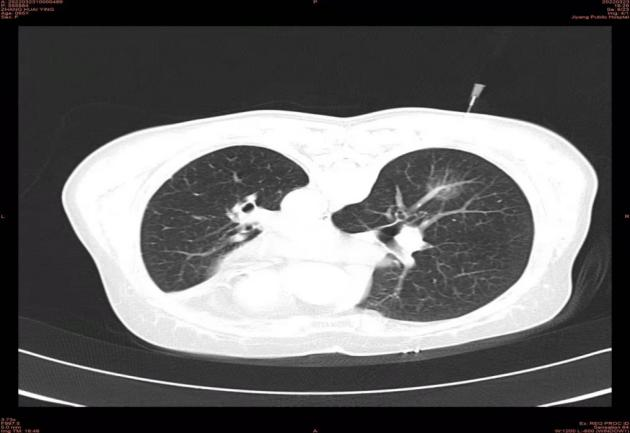

术中

经过一段时间的恢复,3月22日,患者在家属的陪伴下来到我院介入微创科行右肺下叶病变的治疗;3月24日,在影像科及介入微创科团队协同操作下为患者实施了CT引导下经皮微波消融术,整个介入手术操作过程顺利,患者生命体征平稳,无明显不适及并发症发生,术后二十四小时复查胸部CT示微波消融范围理想,病灶位于消融靶心。